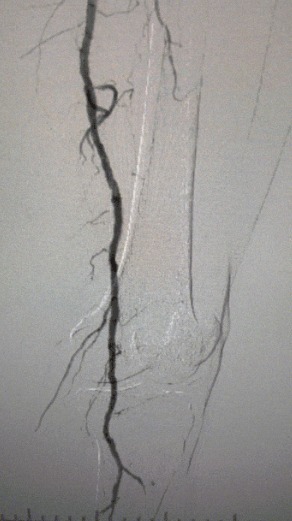

· Esame fisico: legumi femorali deboli; impulsi poplitei e dorsalis pedis assenti; ulcerazione al primo dito sinistro; necrosi al primo e secondo dito destro

· Imaging preoperatorio: stenosi calcificata grave e diffusa nelle arterie degli arti inferiori bilaterali

Dopo la procedura, la stenosi arteriosa è migliorata in modo significativo, il flusso sanguigno è aumentato e la temperatura della pelle è aumentata. Non si sono verificate complicanze postoperatorie. Sia il paziente che il team chirurgico sono stati molto soddisfatti dei risultati.